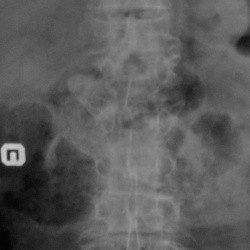

Случай №1 Пожилая женщина пришла на снимок поясницы. После исследования возникли вопросы на предмет перелома тел позвонков. Она точно помнит, что не было. Я считаю что были, просто она не помнит. А...